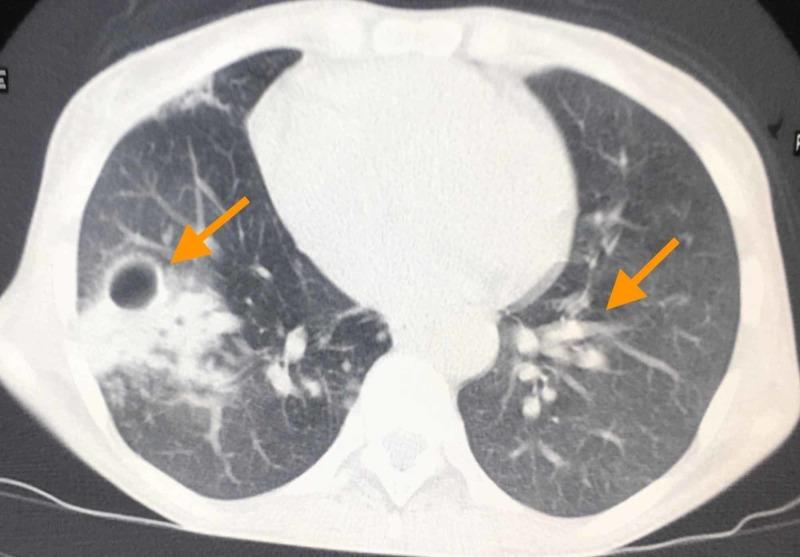

In this article, we discuss the nontuberculous mycobacterial pulmonary disease in a 40-year-old HIV-seropositive female patient. The patient has a history of pulmonary tuberculosis, experienced two years ago. At the time, she was treated successfully with anti-tuberculous therapy. A chest x-ray (CXR) and computed tomography (CT) scan of the chest showed a thin-walled cavitary lesion in the right lung. In addition, the tree-in-bud sign, indicative of airway obstruction, was present on CT imaging. Fluorescence microscopy using auramine staining showed acid-fast bacilli (AFB) in sputum smears on more than two samples. Mycobacterium tuberculosis was not detected in the nucleic acid amplification test in the same sample. The AFB identified were mycobacteria other than tubercle bacilli, i.e., nontuberculous mycobacteria, that cause cavitary lung disease. Culture in liquid media and subsequent molecular analysis showed Mycobacterium avium complex (MAC). The patient is now being treated with a multidrug regimen of antibiotics and has improved, with documented sputum conversion.

在本文中,我们讨论了一名40岁HIV血清阳性女性患者的非结核分枝杆菌肺病。该患者有两年前患肺结核的病史。当时,她接受抗结核治疗后成功治愈。胸部X线(CXR)和胸部计算机断层扫描(CT)显示右肺有薄壁空洞性病变。此外,CT成像显示了提示气道阻塞的树芽征。使用金胺染色的荧光显微镜检查在两份以上痰涂片样本中发现了抗酸杆菌(AFB)。同一样本的核酸扩增试验未检测到结核分枝杆菌。所鉴定的AFB为非结核杆菌,即非结核分枝杆菌,可导致空洞性肺病。液体培养基培养及后续分子分析显示为鸟分枝杆菌复合群(MAC)。该患者目前正在接受多种抗生素联合治疗,病情已改善,痰菌转阴已得到证实。